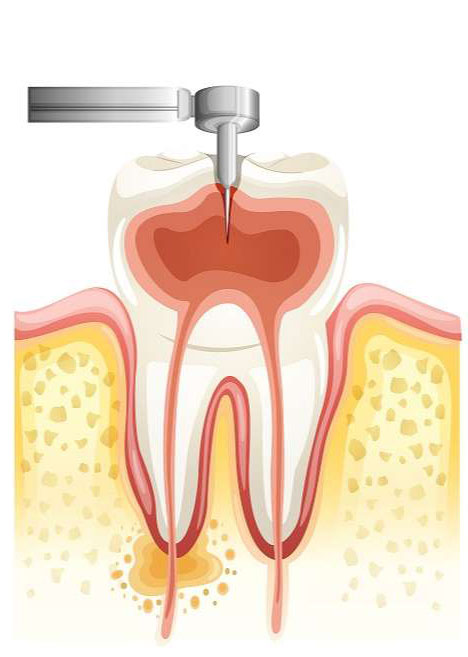

¿CÓMO SE HACE UNA ENDODONCIA?

El primer paso consiste en obtener una completa anestesia del diente. Una vez comprobada la anestesia completa procederemos a entrar en la cámara pulpar que da acceso al interior de las raíces e iremos eliminando el contenido radicular (vasos y nervios) y limpiando las paredes de modo que no quede ningún resto adherido a las mismas. Concluida la limpieza y preparación procederemos a secar el mismo con unas puntas de papel absorbente. Por último, rellenaremos el conducto con unas puntas de gutapercha (resina especial) y un cemento sellador para evitar así que queden espacios vacíos donde las bacterias podrían multiplicarse y producir infecciones posteriores.

Es un tratamiento indoloro pero muy complicado de realizar. Requiere altas dosis de paciencia y atención, pues trabajamos en una zona muy incómoda en la que vemos muy poco y casi todas nuestras acciones son táctiles. La interpretación de la radiografía nos ayuda algo en el tratamiento. Comparando lo que cuesta hacerse una endodoncia con el coste de extraer el diente y colocar un puente que lo sustituya, “quitar el nervio” no es un tratamiento caro. No hace falta hablar de la diferencia económica existente entre hacer una endodoncia y conservar un diente o quitarlo y poner un implante osteointegrado.